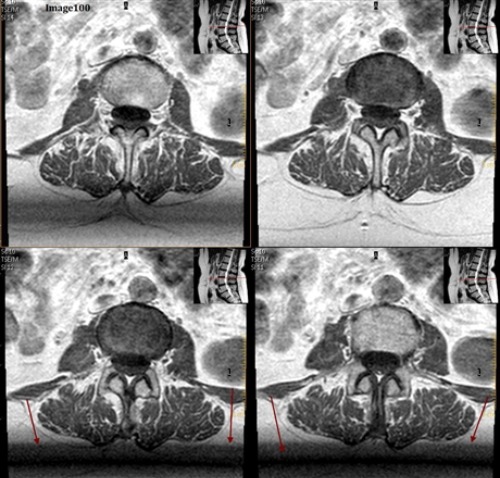

The arrows in Image 100 are pointing to bands of signal variation where adjacent slices appear to be affecting one another. This is an example of:

A. Gibbs truncation

B. Cross talk artifact

C. Dielectric effects

D. Wraparound (aliasing)

E. Partial volume averaging

The cross talk artifact in Image 100 is caused by:

A. Local eddy currents due to the increased conductivity of body tissue

B. When a small matrix is used, it incompletely digitizes the echo by the end of the acquisition

C. Undersampled data at interfaces of differing tissue types

D. The imperfect shape of RF slice profiles, which leads to an unintended excitation of an adjacent slice or tissue

E. Tissue outside the FOV is undersampled

One can correct for the cross talk artifact seen in Image 100 by:

A. Increasing interslice gap

B. Interleaved slice order

C. Acquiring stacks as complete packages

D. All of the above